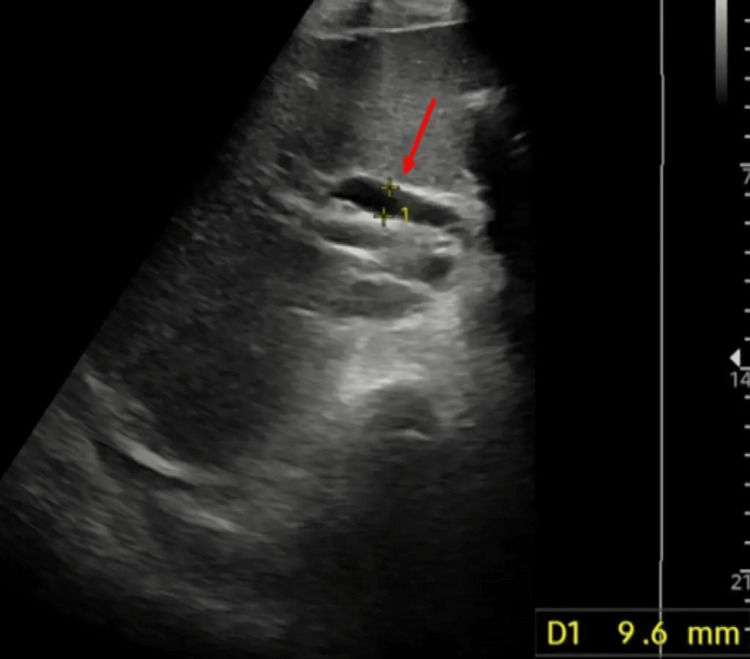

Liver blood tests screening for possible hepatic, metabolic, and genetic aetiologies were inconclusive and an inpatient ultrasound scan (USS) of the abdomen showed a normal size liver with a normal ECHO pattern and no obvious focal lesions. However, the gallbladder was found to be grossly distended with sludge and debris within the lumen. The proximal common bile duct was seen to be dilated to 9.6 mm and the pancreas and distal duct were obscured by overlying bowel gas with no obvious intrahepatic tree dilatation seen (Figure 1).